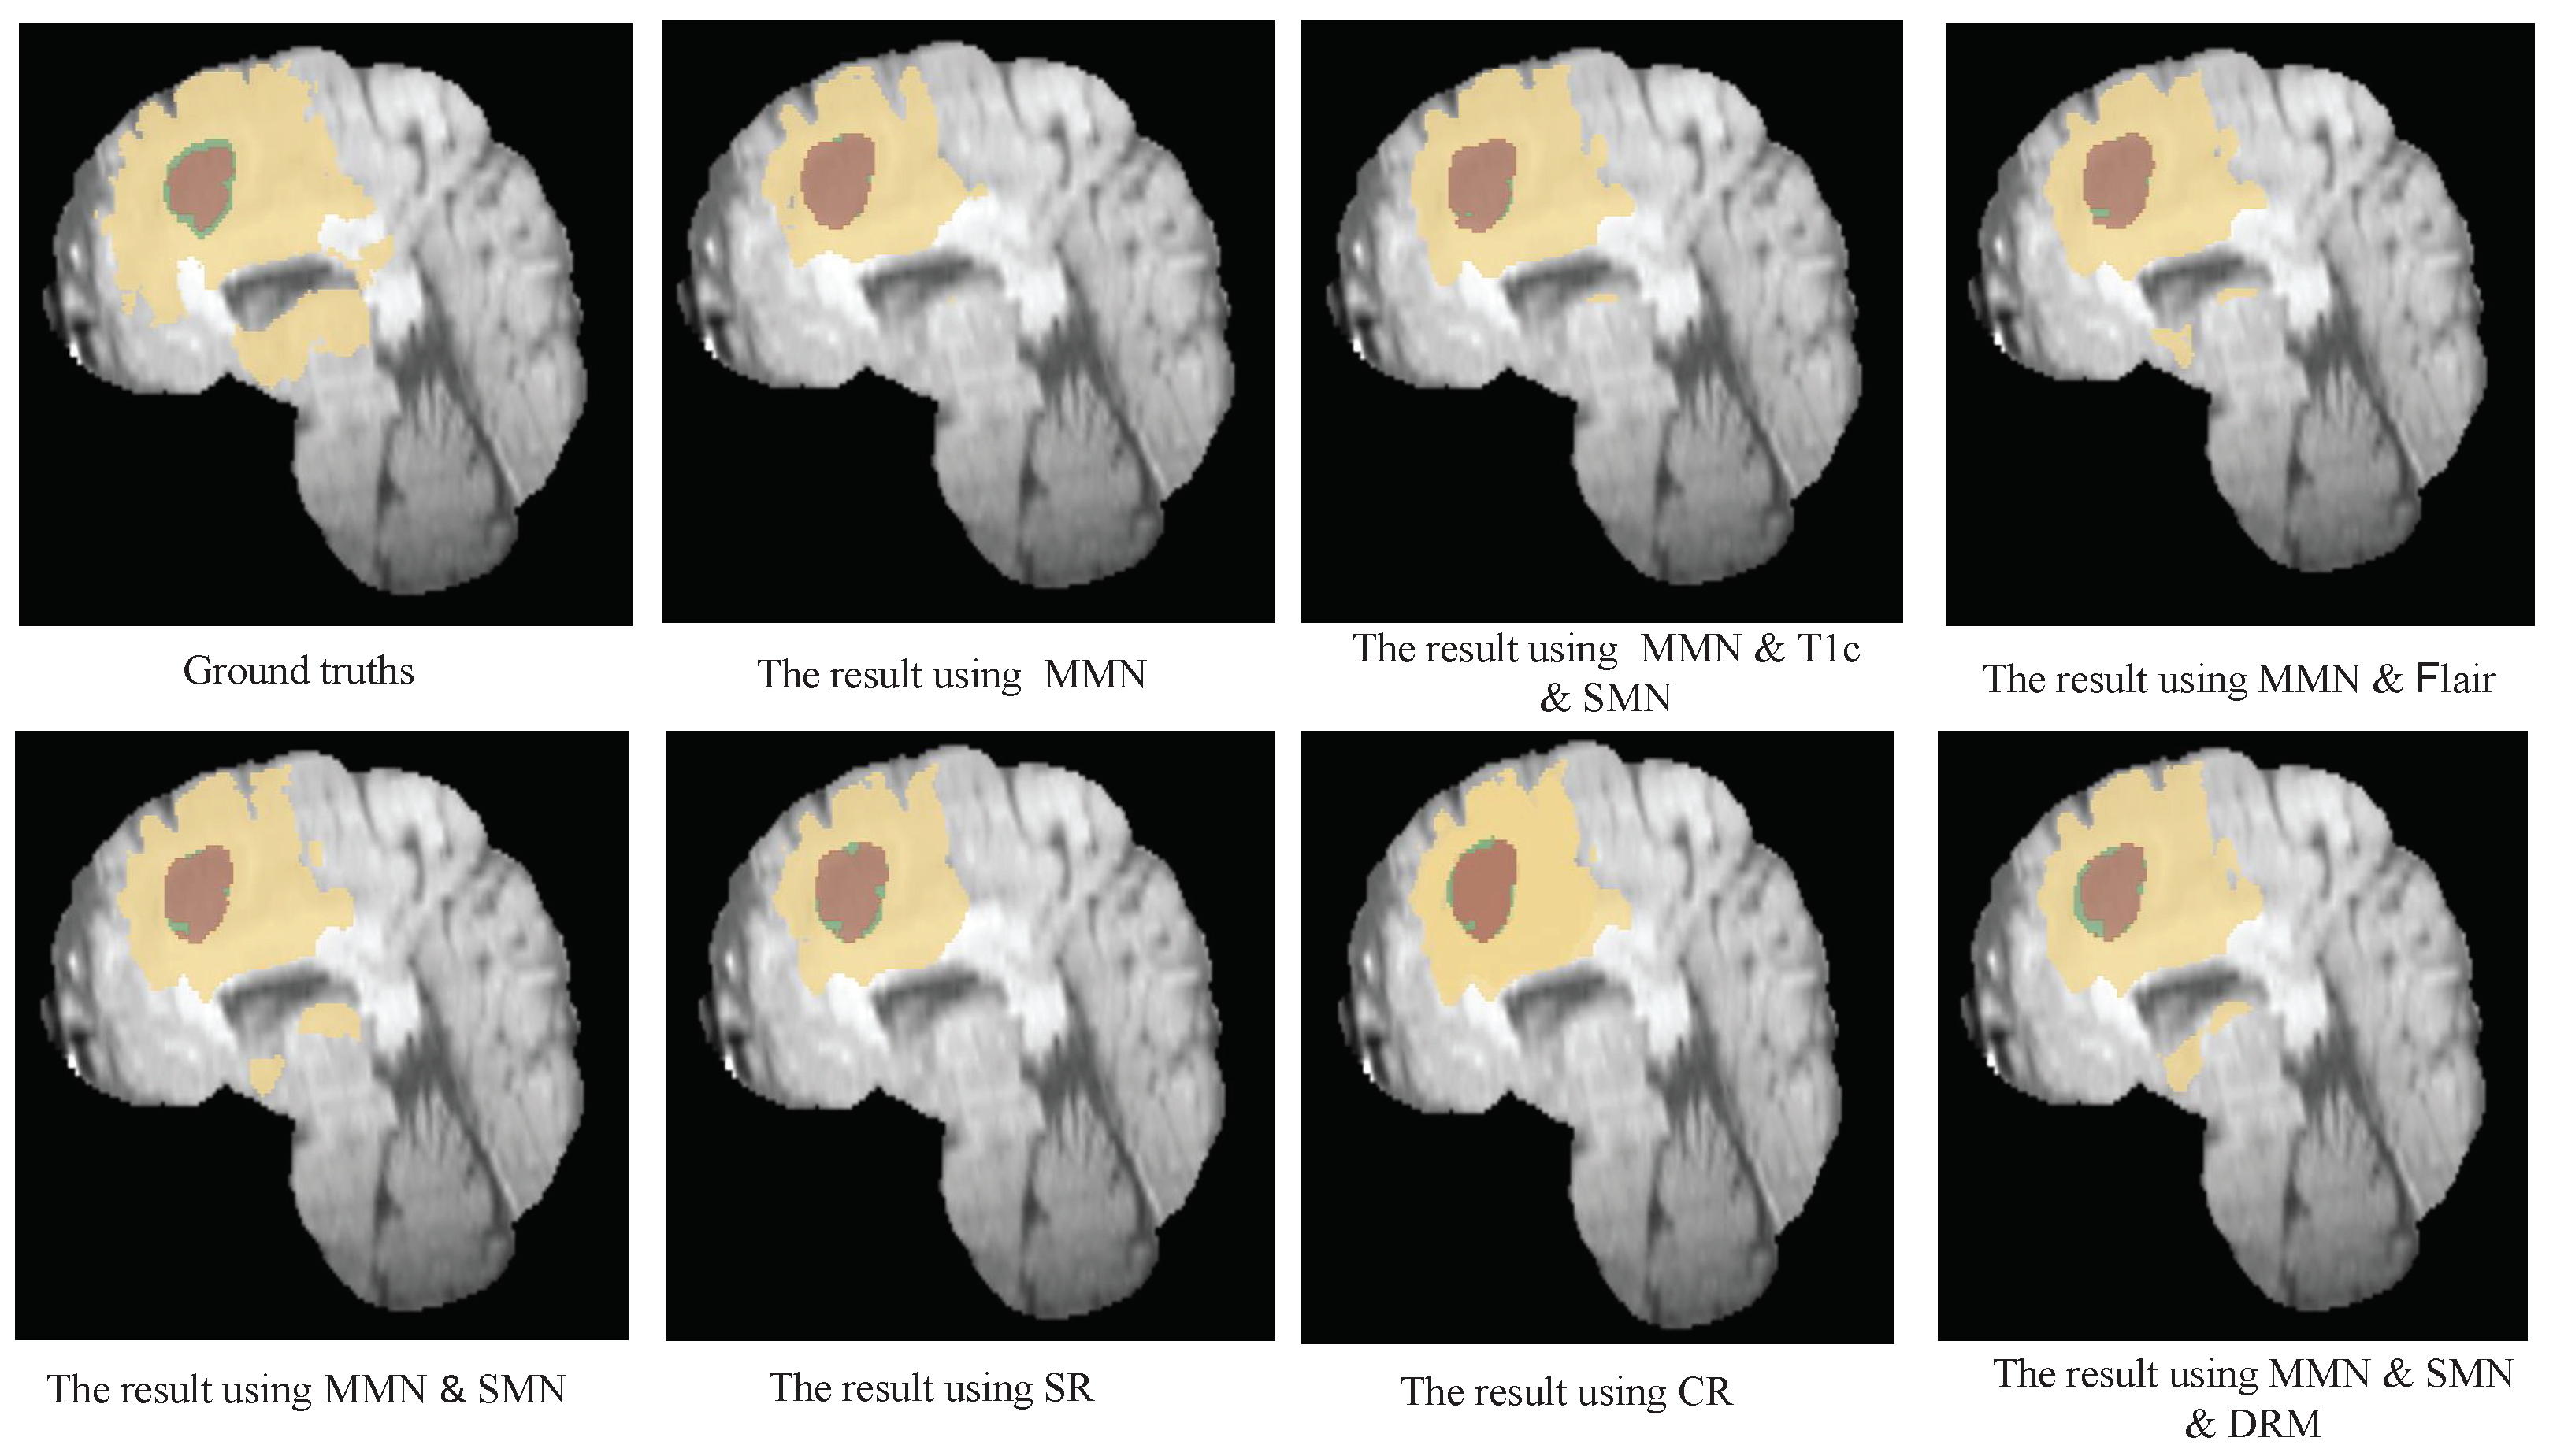

6.1. The Results of Combining MMN and SMN

6.2. Validity of Dual DRM

| MMN | 0.814 | 0.795 | 0.834 | 4.461 | 0.891 | 0.948 | 0.868 | 7.904 | 0.855 | 0.920 | 0.841 | 5.370 |

| MMN & Flair | 0.817 | 0.798 | 0.827 | 3.599 | 0.896 | 0.940 | 0.883 | 8.129 | 0.867 | 0.892 | 0.851 | 5.362 |

| MMN & T1c | 0.823 | 0.811 | 0.835 | 3.897 | 0.904 | 0.952 | 0.873 | 7.524 | 0.885 | 0.952 | 0.848 | 4.629 |

| MMN & SMN | 0.821 | 0.795 | 0.861 | 3.615 | 0.909 | 0.953 | 0.879 | 8.130 | 0.879 | 0.957 | 0.855 | 5.321 |

| NoDRM | 0.815 | 0.876 | 0.876 | 3.474 | 0.913 | 0.945 | 0.884 | 7.727 | 0.860 | 0.925 | 0.842 | 4.764 |

| SR | 0.832 | 0.788 | 0.880 | 3.404 | 0.918 | 0.932 | 0.901 | 7.666 | 0.876 | 0.929 | 0.826 | 5.836 |

| CR | 0.868 | 0.775 | 0.882 | 3.478 | 0.916 | 0.947 | 0.891 | 7.535 | 0.868 | 0.924 | 0.850 | 4.807 |

| MMN & SMN & DRM | 0.898 | 0.807 | 0.893 | 3.298 | 0.923 | 0.945 | 0.920 | 7.508 | 0.879 | 0.948 | 0.866 | 5.109 |